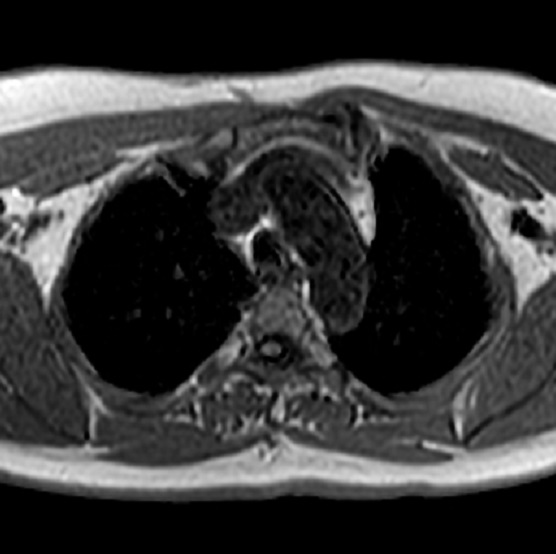

Aspect radiologique IRM de

même cas en coupe axial ponderee sur T2 . Zone

oedemateuse du lesion est hypersignal ( hyperintense

) en vue tres nette sur ce coupe . |